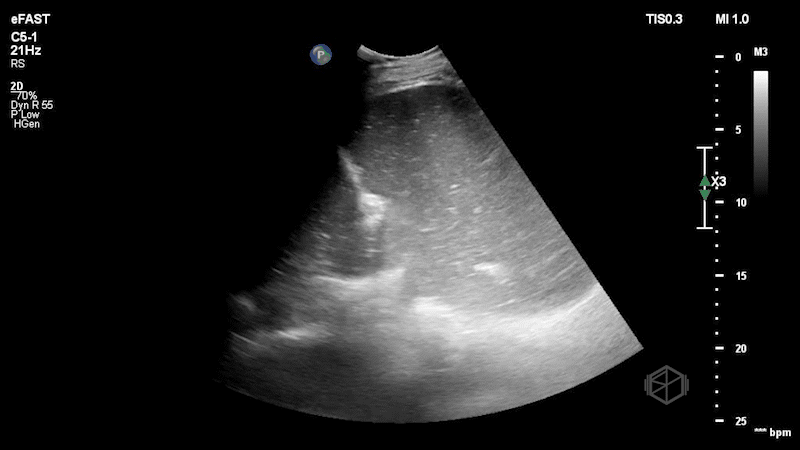

Left upper quadrant ultrasound demonstrating a hiatal hernia with stomach herniating through.

The stomach is swirling with food contents and is visible on both sides of the diaphragm.